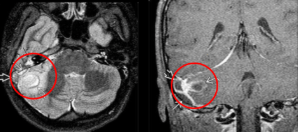

Q

Cuál es tu diagnóstico?

A

Otitis media

La RM está indicada en las complicaciones de la otitis media, ¿Coque veras en la secuencia T1 y T2?

T1: masa hipointensa en oído medio

T2: masa híper intensa en oído y mastoides